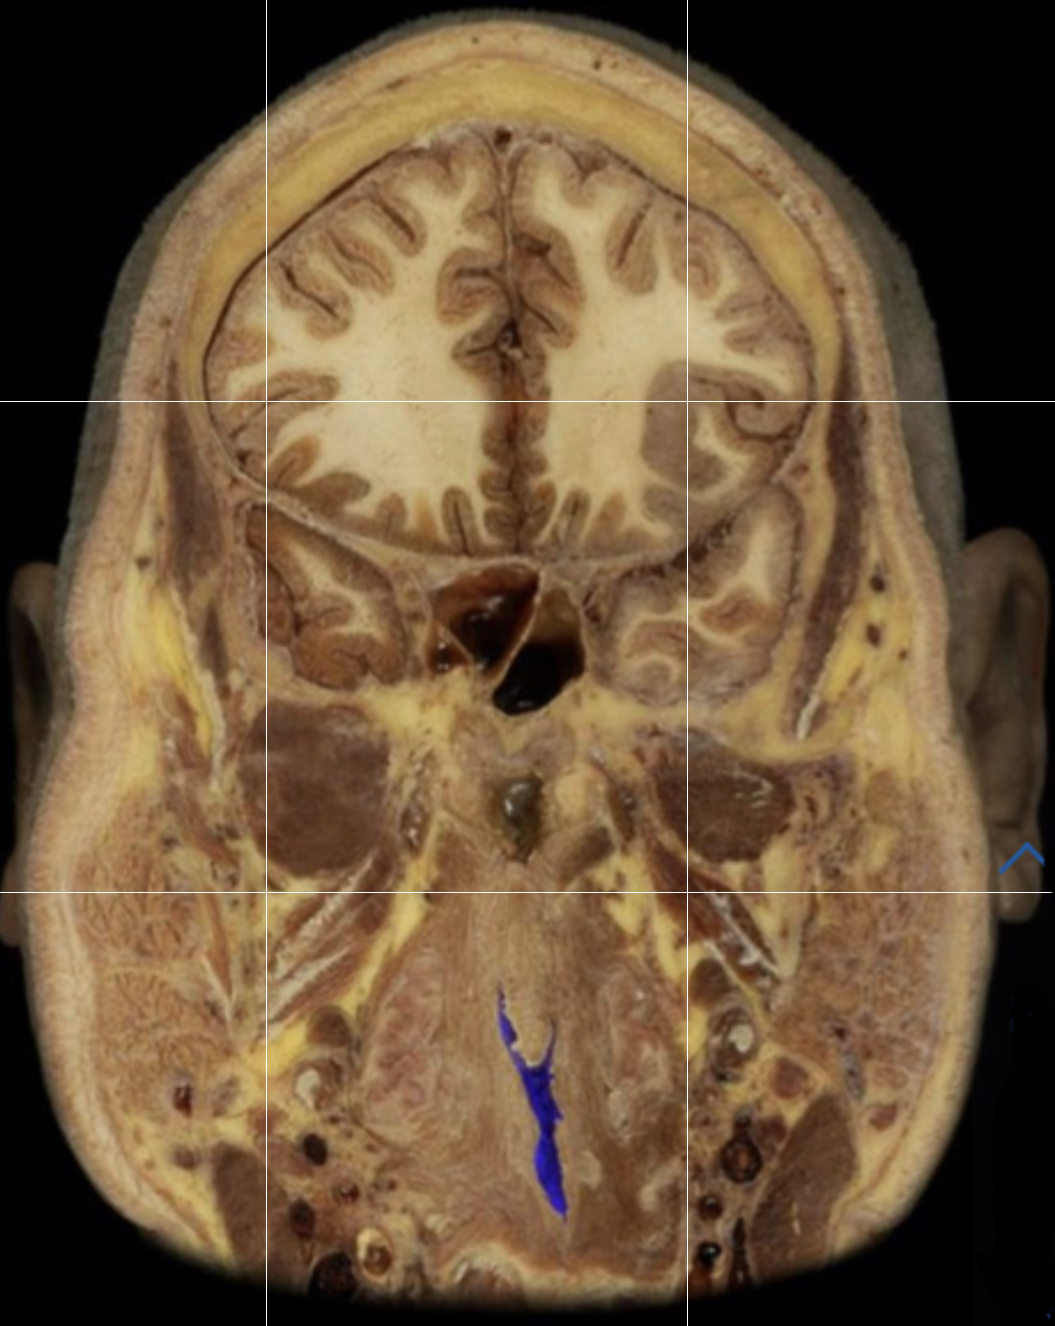

What structure is highlighted in blue?

Pleural cavity